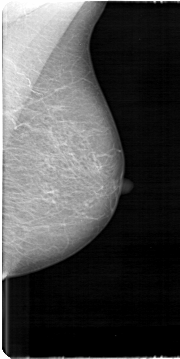

D_4103_1.LEFT_MLO

D_4103_1.LEFT_CC

LEFT_CC LINES 5056 PIXELS_PER_LINE 2146 BITS_PER_PIXEL 12 RESOLUTION 43.5 NON_OVERLAY

LEFT_MLO LINES 5371 PIXELS_PER_LINE 2686 BITS_PER_PIXEL 12 RESOLUTION 43.5 NON_OVERLAY